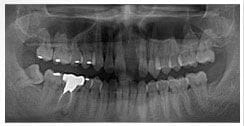

X 光片

術後X光片